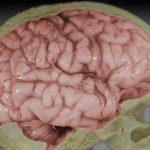

Descubren un cerebro vitrificado por la erupción del Vesubio

Existen túneles secretos entre el cráneo y el cerebro